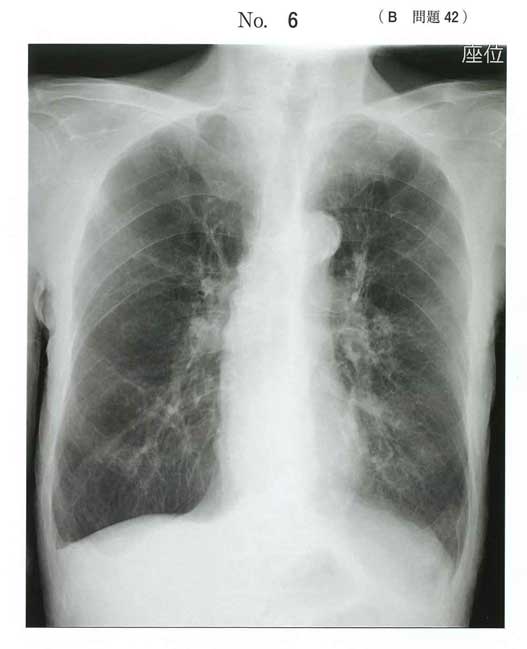

B問題

| タイトル:120B-42 | コメント数:3 |

| 42 | 120B-42 | 3 | |

COPD急性増悪でABCアプローチ。

感染症にステロイドはダメじゃね?みたいな浅い勉強だと間違えるかも?